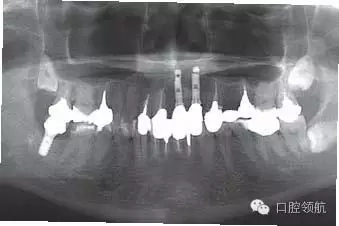

圖5 上部修復(fù)完成后的全景X線片。